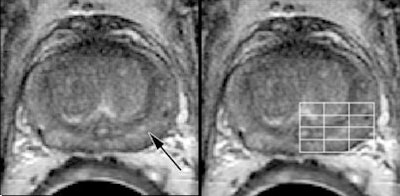

![]() |

| A 60-year-old patient with biopsy-proven recurrent prostate cancer in the left side of prostate. Axial T2-weighted MR image (left) shows findings consistent with post-treatment changes (arrow). However, MR spectroscopic image (right) shows areas of malignant metabolism (line grid). Images courtesy of Radiology. |